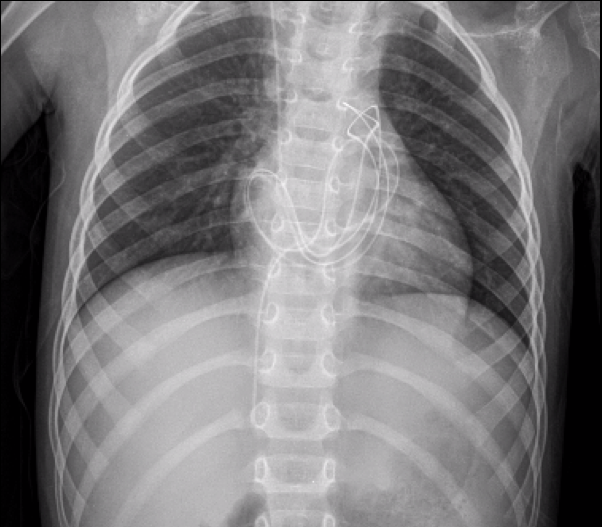

Ingresó a nuestra Institución, sin clínica neurológica progresiva, a través de la consulta ambulatoria con el Servicio de Neumonología. Se realizó una radiografía de tórax de rutina (Figura 1) y se completó estudios con Tomografía de tórax (Figura 2), en la que se evidenciaba migración intratorácica transdifragmatica del catéter distal de la DVP e infiltrado pulmonar derecho, asociado a fibrosis y retracción mediastínica. Se realizó Tomografía cerebral, evidenciando mayor dilatación ventricular en comparación al estudio previo. El paciente ingresó a quirófano para revisión del sistema valvular y recolocación de catéter distal en cavidad peritoneal. Evolucionó favorablemente y fue dado de alta con controles ambulatorios. Cinco meses después, el Servicio de Cirugía General realizó una neumonectomía estándar derecha, a través de toracotomía posterolateral, debido a la extensa destrucción pulmonar. A la inspección quirúrgica, no se observó lesión diafragmática. El informe histopatológico de la muestra evidenció fibrosis, bronquiectasias e infiltrado inflamatorio crónico con evidencia de sobreinfección aguda (Figura 3).

Figura 1: Radiografías de tórax y abdominal del Caso 1, que muestran un catéter distal migrado hacia el tórax (flecha roja) con un infiltrado pulmonar derecho y desplazamiento de la silueta cardíaca y las vías respiratorias (flecha negra).